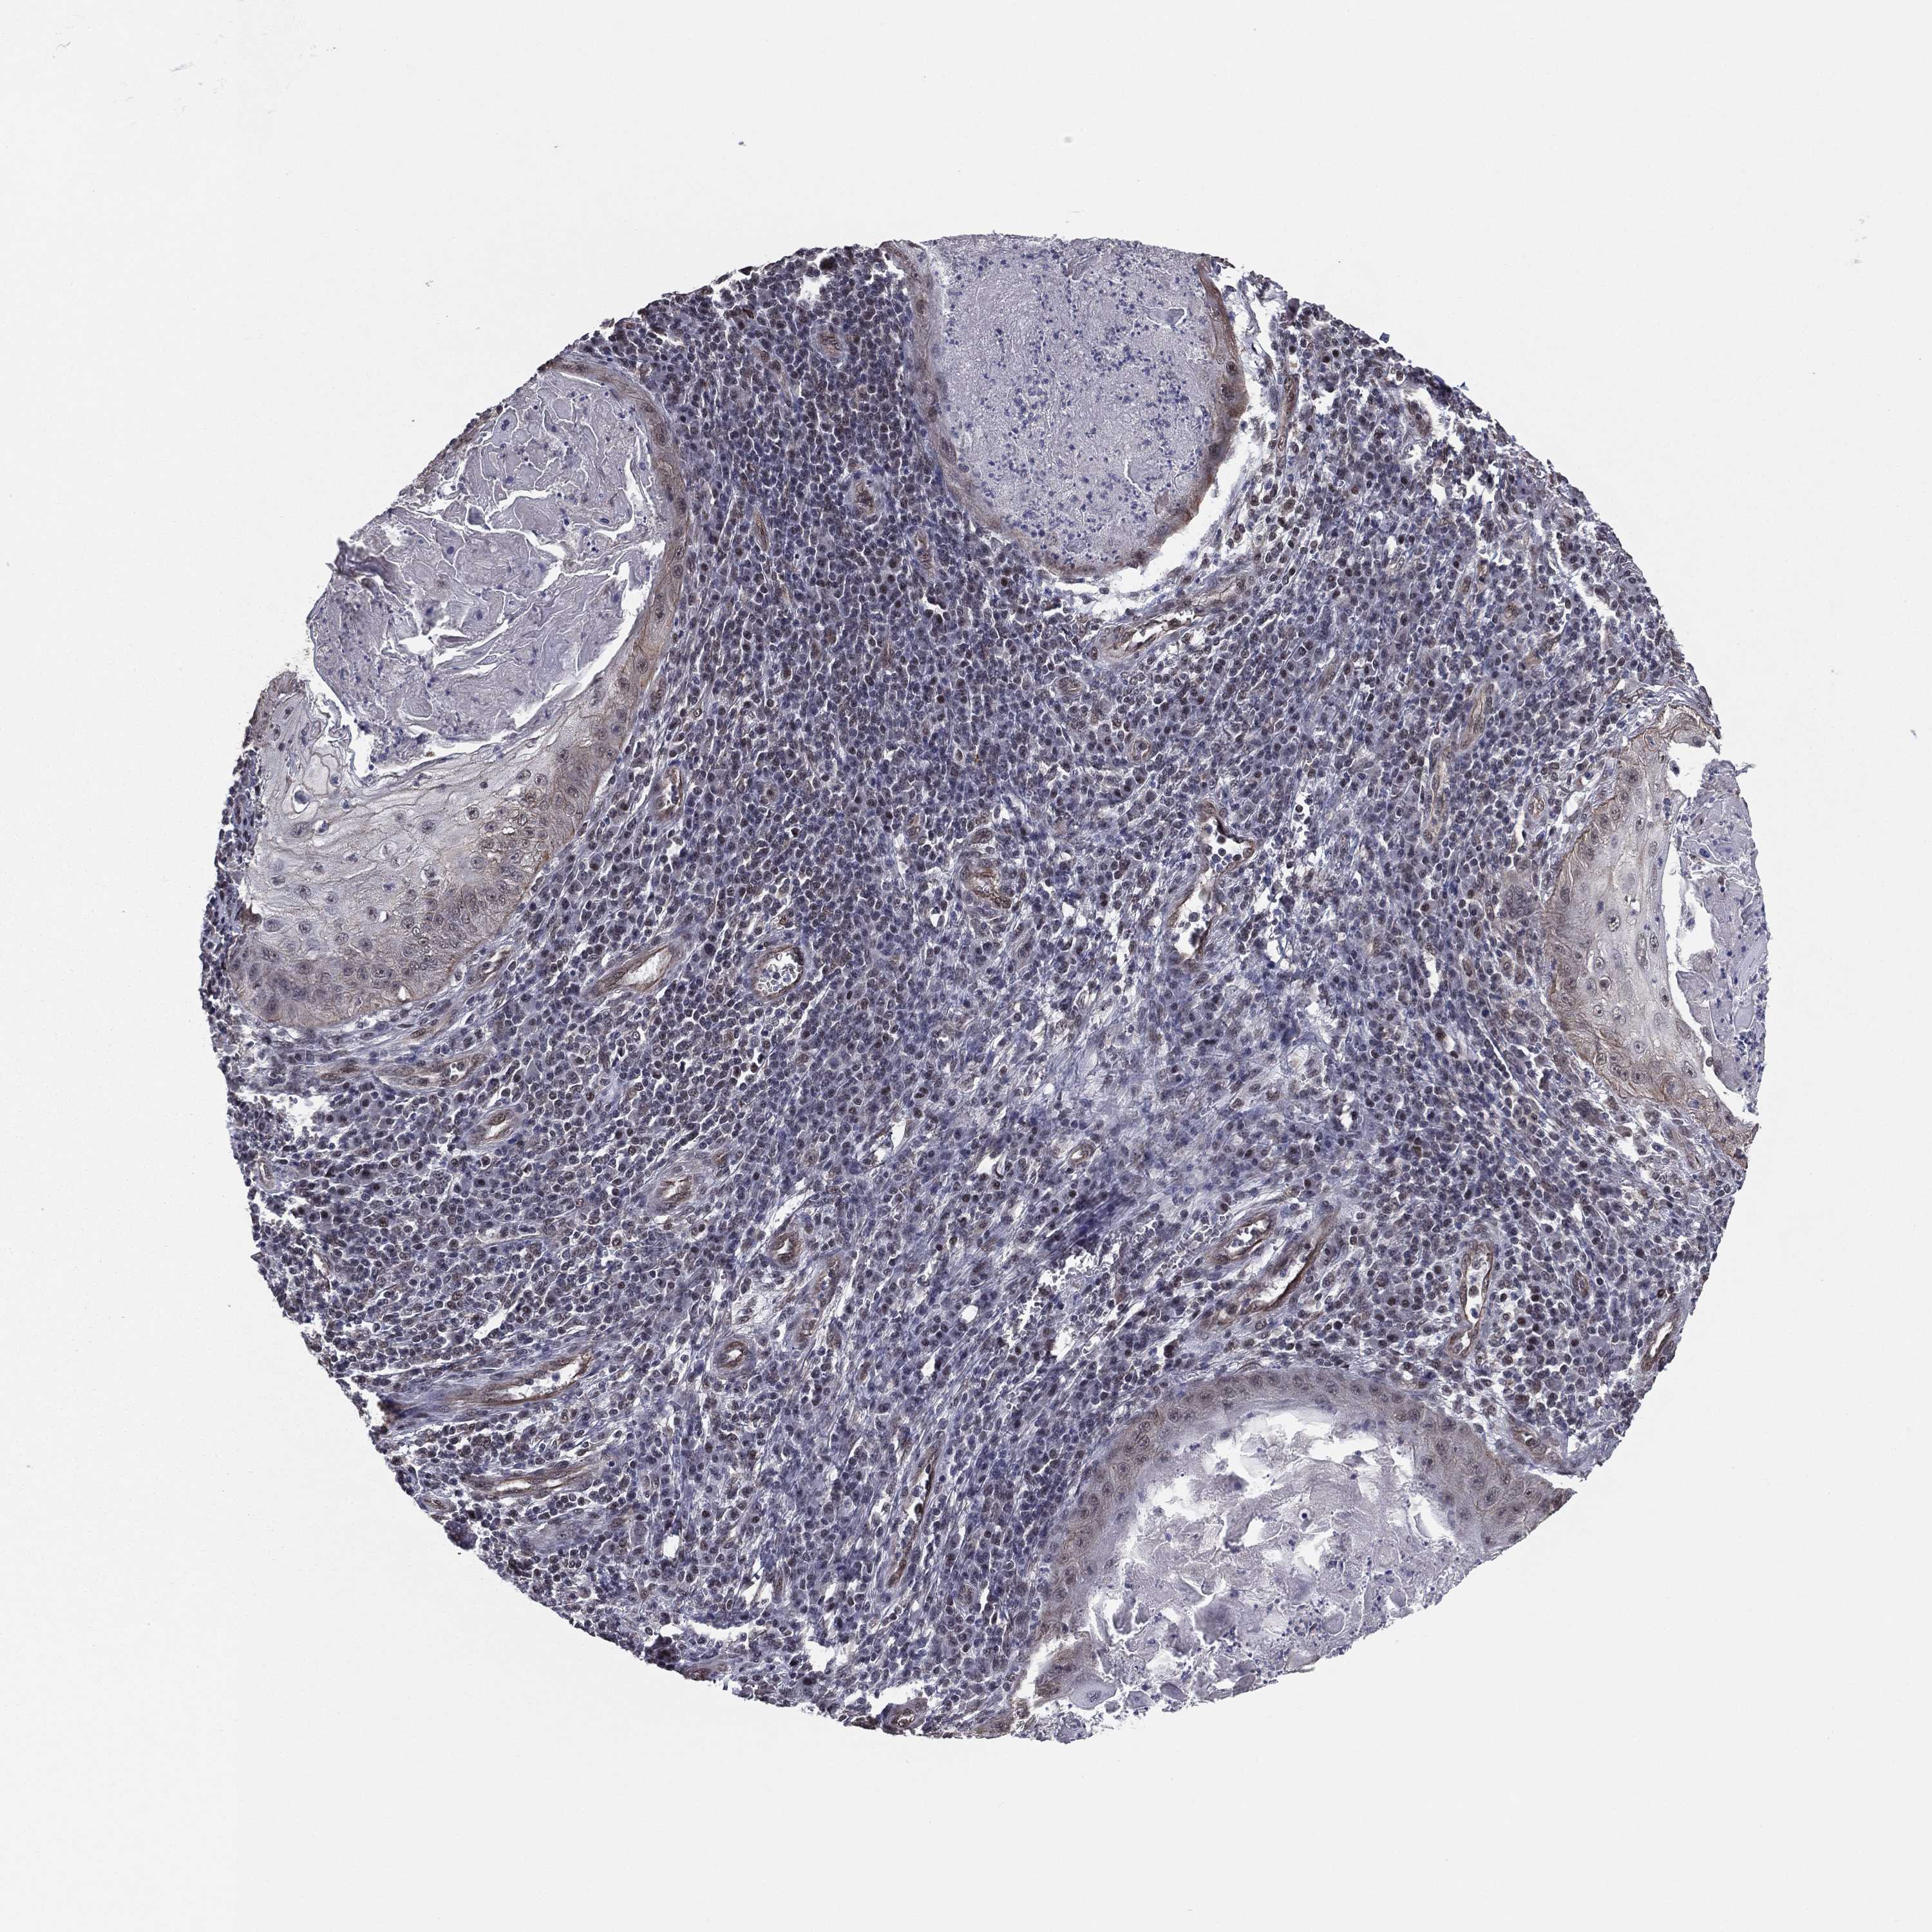

SKIN CANCER - Protein expressioni

A mouse-over function shows sample information and annotation data. Click on an image to view it in a full screen mode. Samples can be filtered based on level of antibody staining by selecting one or several of the following categories: high, medium, low and not detected. The assay and annotation is described here.

Antibody stainingi

Antibody staining in the annotated cell types in the current human tissue is reported as not detected, low, medium, or high, based on conventional immunohistochemistry profiling in selected tissues. This score is based on the combination of the staining intensity and fraction of stained cells.

Each image is clickable and will lead to virtual microscopy that enables deeper exploration of all samples and also displays staining intensity scores, fraction scores and subcellular localization as well as patient and tissue information for each sample.

Antibody HPA004174

Antibody CAB002617

Staining

High

Medium

Low

Not detected

Intensity

Strong

Moderate

Weak

Negative

Quantity

>75%

75%-25%

<25%

None

Location

Nuclear

Cytoplasmic/membranous

Cytoplasmic/membranous,nuclear

Basal cell carcinoma

Squamous cell carcinoma, NOS